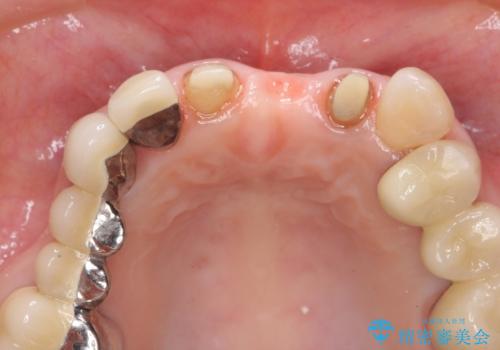

歯肉縁下カリエスも認められるため、挺出を行いセラミックブリッジを審美的に新製します。

挺出について

虫歯が深くなった場合、挺出や歯周外科を行い歯周組織の状態を改善することでより安定した状態で予知性の高いセラミックブリッジを製作することが可能となります。

- 47万円(仮歯×3・ファイバーコア×2・ジルコニアクラウン×3 歯の挺出)費用は治療当時の料金となります